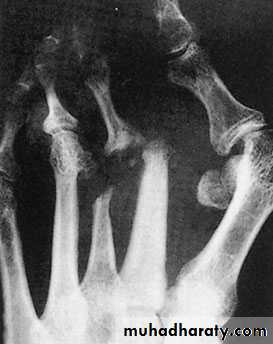

Rheumatoid arthritis of the ankle and foot:

The foot is affected as common as the hand and the disease pass in its three stages,1st. stage of synovitis that affects ankle, intertarsal and other small joints, also affects synovial tendon sheath of different tendons mainly the tibialis posterior and the peronei.

2nd.stage of erosion of the articular cartilage and tendons that can be torn.

3rd. stage of severe deformity and dysfunction with the characteristic deformities of foot valgus, forefoot splaying, hallux valgus and toe clawing.

Patient having progressive pain and discomfort with difficulties in shoe wear and walking. There is limitation of movements and gradual development of deformities, callosities and corns.X-ray: May show the joint erosions and foot deformities.